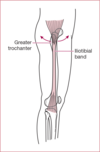

External snapping hip

pain in lateral thigh due to a tight IT band or gluteus maximus snapping over the greater trochanter

Commonly mistaken for greater trochanteric bursitis

Gluteus medius tendonitis/tendinopathy

What is greater trochanteric bursitis?

inflammation of the subgluteus maximus bursa located just deep to the gluteus maximus muscle and just superficial to the gluteus medius tendon as it inserts onto the greater trochanter